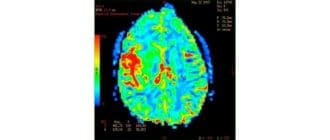

コンピュータ断層撮影(CT)またはコンピュータ断層撮影(CAT)スキャンは、複数のX線からのデータを結合して、体内の構造の詳細な画像を生成します。 CTスキャンは、身体の「スライス」または断面の2次元画像を生成するが、こ […]